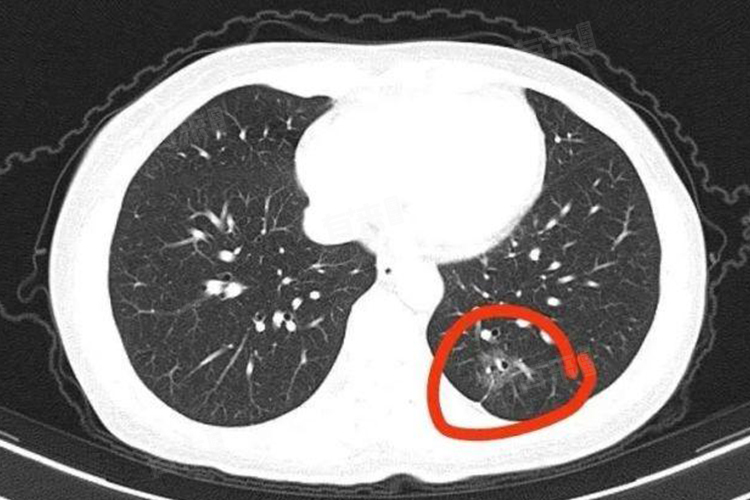

- CT可以进行薄层扫描。通过对肺部进行薄层扫描,能够获取更详细的肺部信息,对结节的形态、大小、密度等特征进行更准确的分析。例如,早期肺癌的结节可能会出现边缘毛刺、分叶征、空泡征等特殊形态,CT的薄层扫描有助于医生清晰地观察到这些特征,从而提高对早期肺癌的诊断准确率。

- CT的三维重建技术发挥了重要作用,可以将肺部的二维图像进行三维重建,从不同角度观察肺部病变,更加全面地了解结节与周围组织的关系,判断结节的良恶性。对于早期肺癌,准确判断肿瘤的位置、范围以及与周围血管、支气管的关系,对于制定后续的治疗方案至关重要。